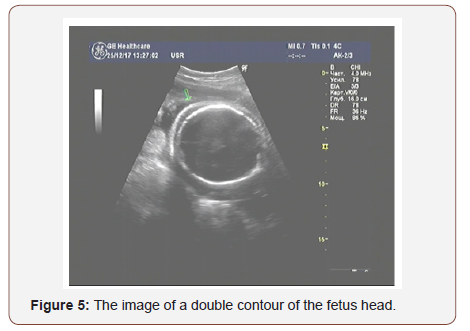

On the day before the operation, a repeated ultrasonic examination showed the ultrasonic signs of fetal dropsy: a double contour of the head (Figure 5) and free fluid in the abdominal cavity of the fetus.

The outcome-live, premature female fetus born through a cesarean delivery, with pronounced signs of a non-immune dropsy of the fetus, weighing 1600 grams, 40cm long. The Apgar score was 4 points on the 5th minute after birth.